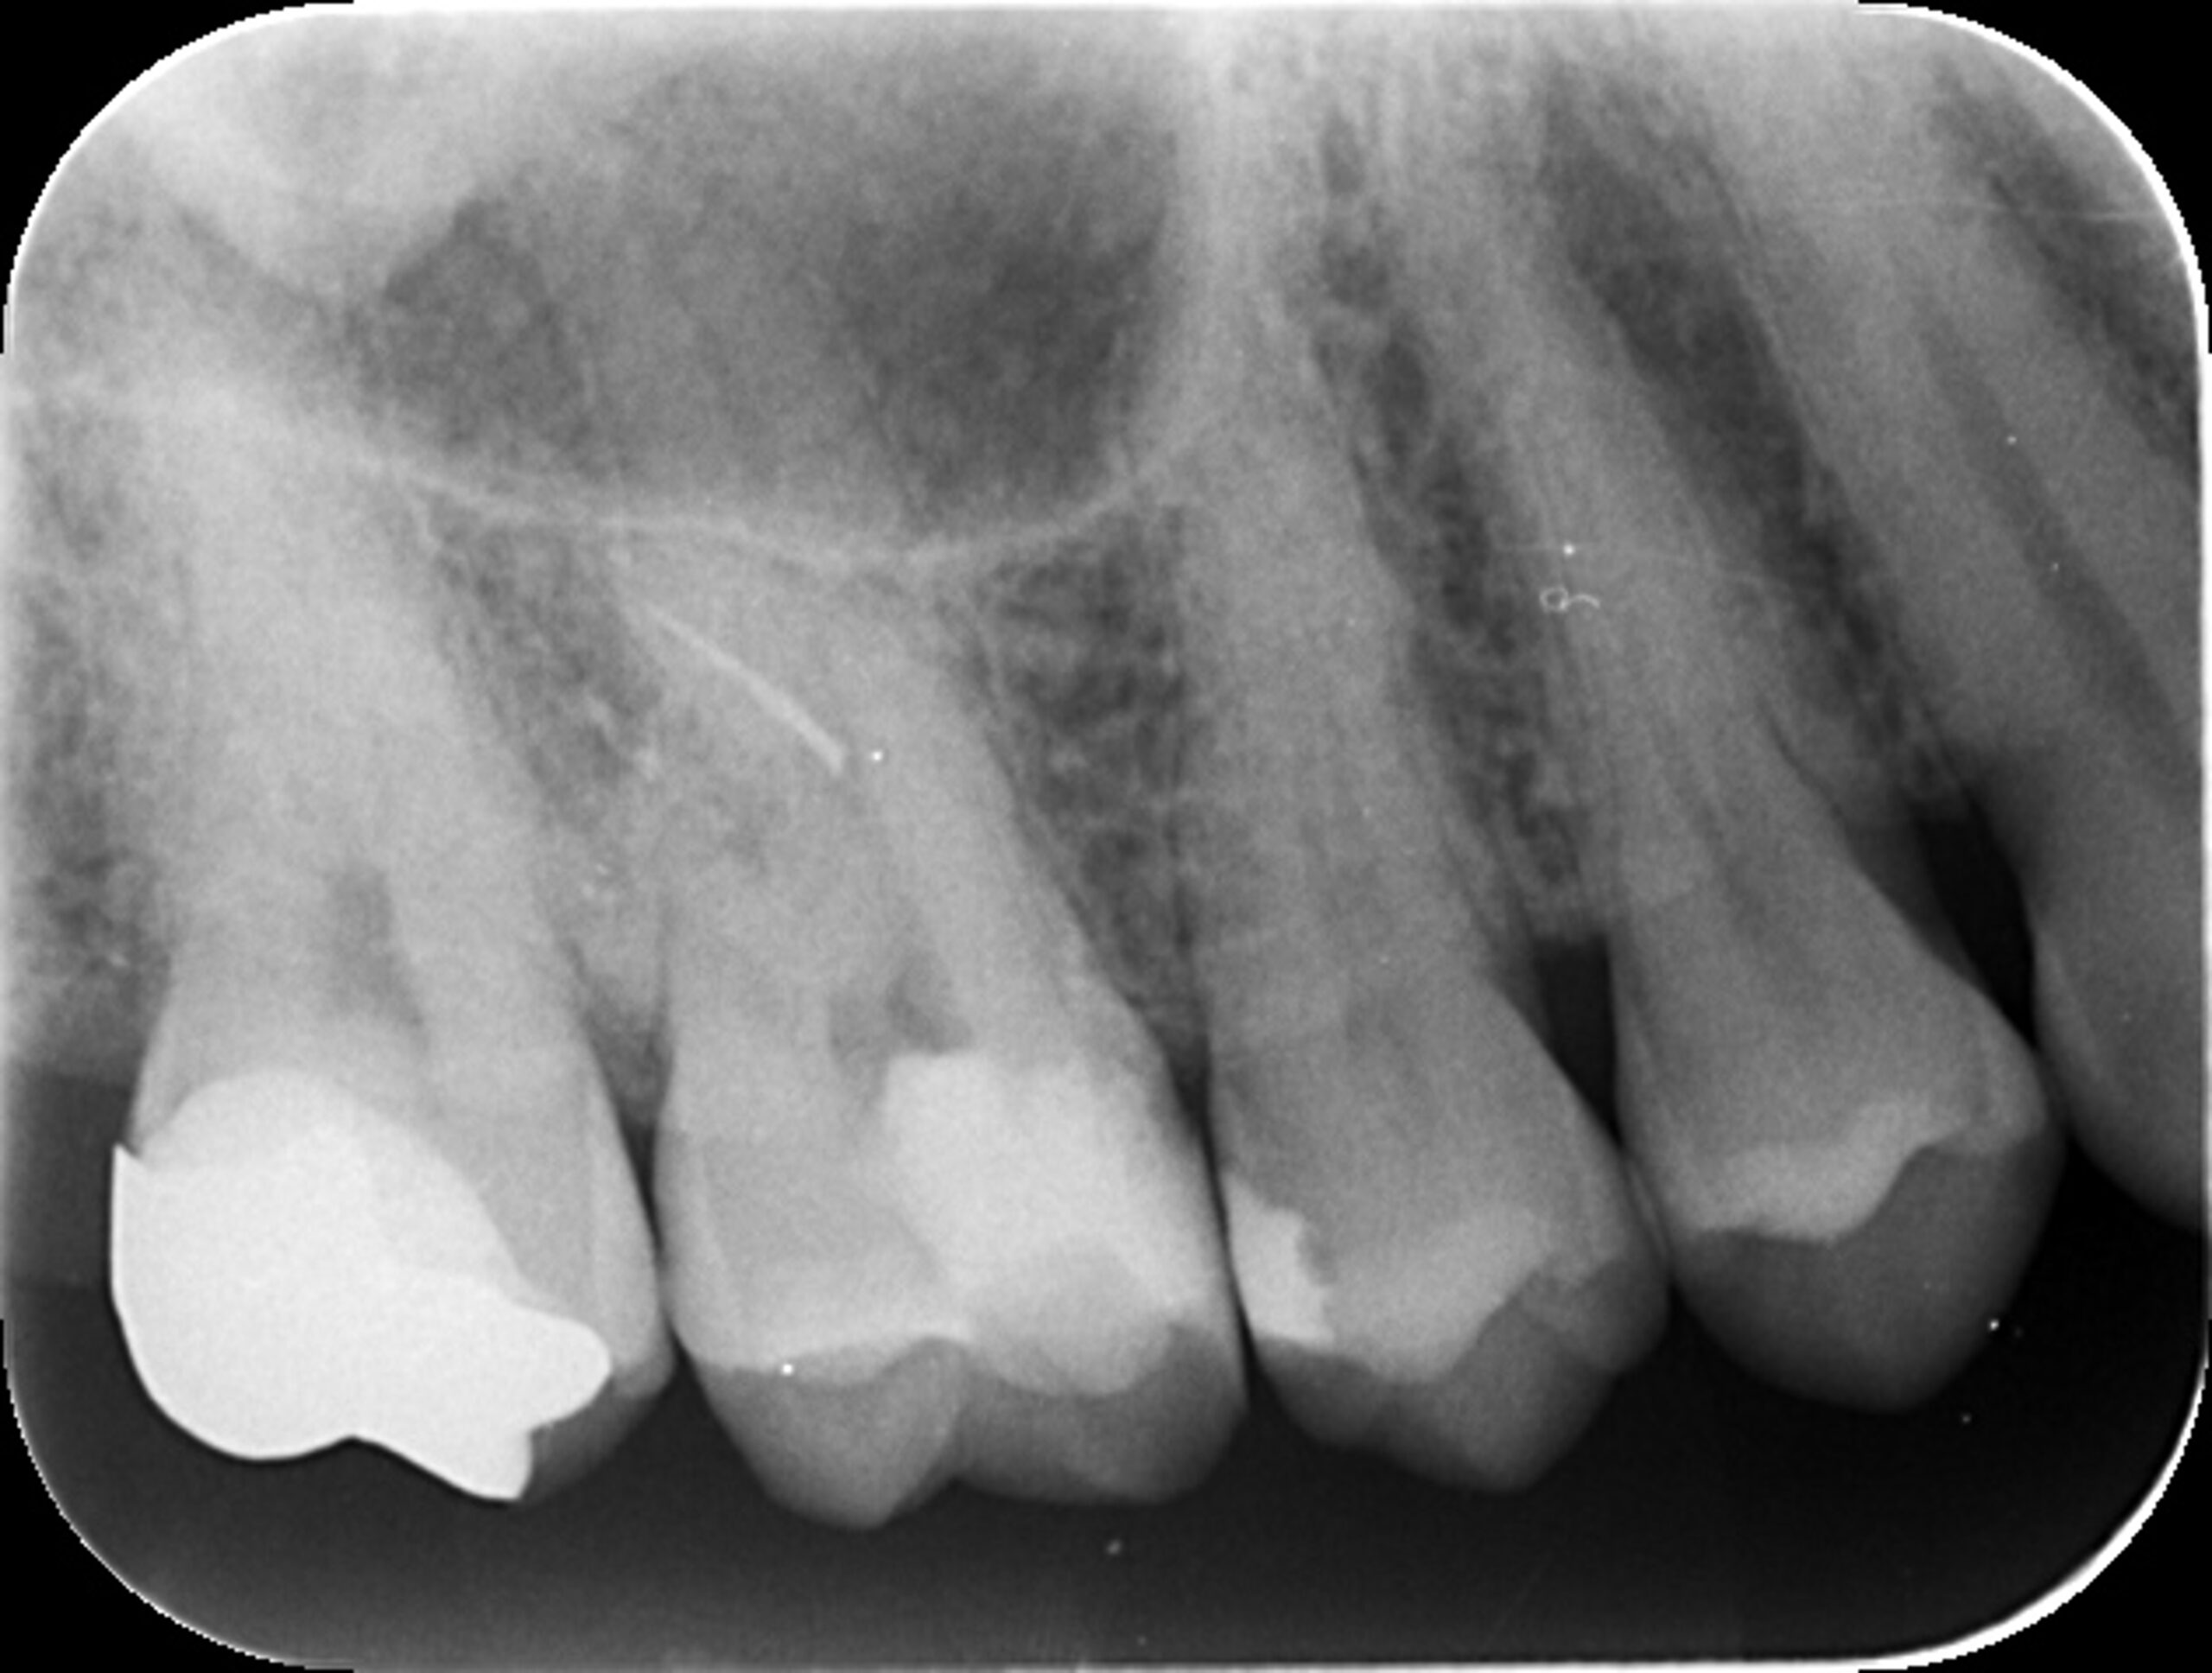

症例2

BEFORE |

AFTER |

| 患者様データ | 80代 男性 |

| 来院時の主訴 | 「右上の奥歯が噛むと痛い。」 |

| 医院の診断 | 虫歯の再発、慢性根尖性歯周炎、炎症による歯髄狭窄 |

炎症を起こしてからかなり時間が経っているためか、神経が確認できない程に歯髄狭窄を起こしていました。 ラバーダム防湿とマイクロスコープを使用して丁寧に治療を行いました。 再根管治療のため、殺菌性があり歯を補強することのできる根管充填材料を使用しています。 |